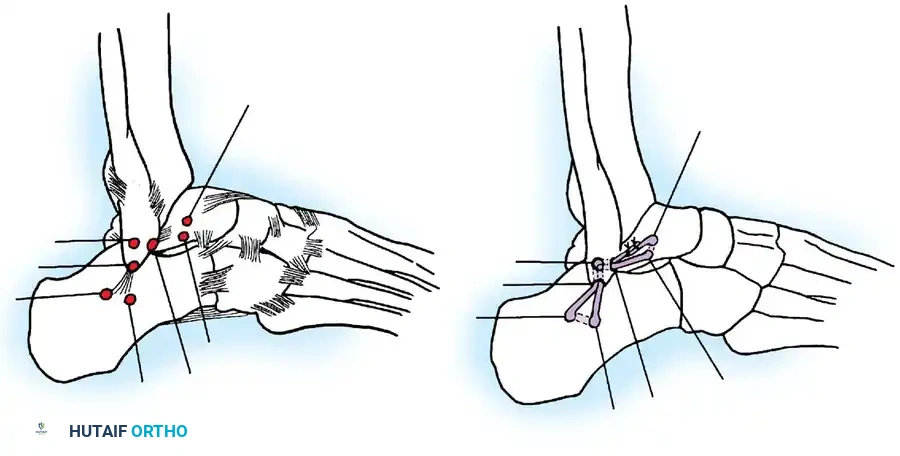

The modified Broström-Gould procedure remains the gold standard for anatomic repair of the lateral ligamentous complex.

Surgical Technique:

1. Positioning: The patient is placed supine with a bump under the ipsilateral hip to internally rotate the leg, bringing the lateral malleolus into direct view. A thigh tourniquet is applied.

2. Incision: A 4- to 5-cm curvilinear incision is made along the anterior border of the distal fibula, extending toward the sinus tarsi.

3. Dissection: Care is taken to identify and protect the intermediate dorsal cutaneous branch of the superficial peroneal nerve superiorly and the sural nerve inferiorly.

4. Capsulotomy: The extensor retinaculum is identified and mobilized. A vertical arthrotomy is performed 2 mm anterior to the fibular margin, leaving a small cuff of tissue for repair.

5. Joint Inspection: The joint is inspected for osteochondral lesions or loose bodies.

6. Ligament Repair: The torn ends of the ATFL and CFL are identified. If the tissue is robust, direct end-to-end repair is performed using non-absorbable sutures (e.g., 0 or 2-0 FiberWire). If the ligaments are avulsed from the fibula, suture anchors (typically 2.5 mm to 3.0 mm) are placed into the anterior border of the lateral malleolus.

7. Gould Modification: The inferior extensor retinaculum is mobilized and advanced proximally and laterally over the repaired ligaments, suturing it to the fibular periosteum. This imbrication reinforces the repair, limits inversion, and helps address subtalar instability.